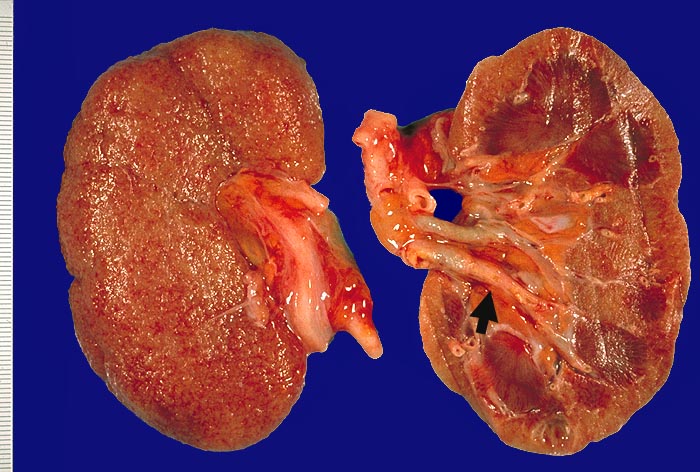

PathoPic ID 1903 - Noduläre Glomerulosklerose bei Diabetes mellitus Typ II

Noduläre Glomerulosklerose bei Diabetes mellitus Typ II

Systemerkrankung/Immunpathologie

Niere

Niere, Harnwege

Gelbverfärbung der Schnittfläche. Oberfläche fein granuliert. Die Arterien sind bis weit in die Peripherie gut sichtbar aufgrund von

Atheromen.

Termianale Niereninsuffizienz.

Makroskopie